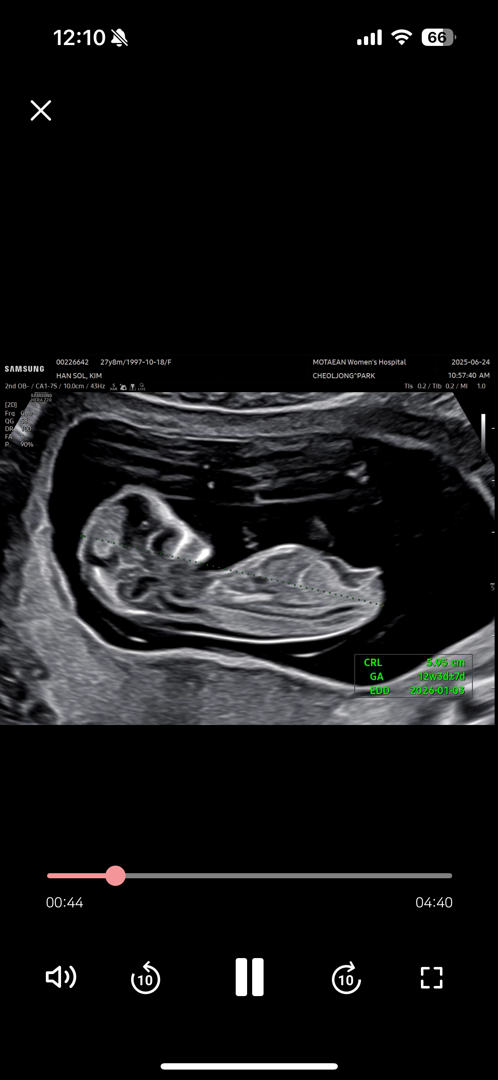

12주2일 각도법 잘 보시는 분 계실까요?!

딸일까요 아들일까요?!!